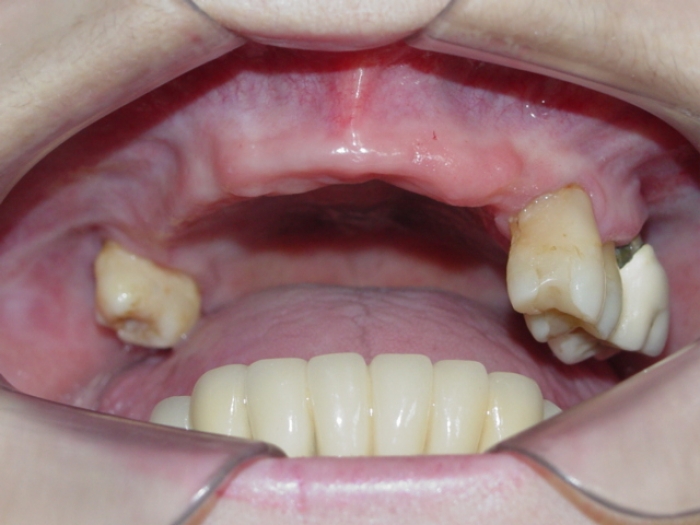

Imagens iniciais